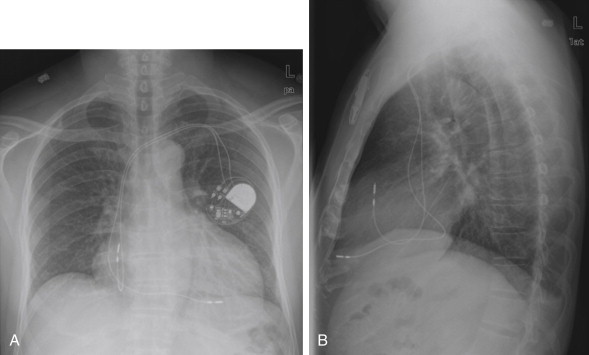

Lateral Upright Chest X-ray View: Retrosternal Space, Retrocardiac Space, and the Spine Sign

The lateral chest x-ray provides important diagnostic information. Unfortunately, this view is usually not obtained when a portable x-ray examination is performed—another good reason to send the patient to the radiology suite for imaging if the clinical condition permits this. The lateral view (Figure 5-16 ) reveals the retrosternal space, which overlies the heart and mediastinum on a frontal projection. This space is usually quite lucent (black) because of the presence of a low-density epicardial fat pad and sometimes lung segments—but when occupied by a soft-tissue mass, this space may appear radiodense (white) (Figure 5-17 ). The lateral chest x-ray also reveals the retrocardiac space. This space normally should be quite lucent (black) (see Figure 5-16). Lower lobe pneumonias may be evident on the lateral view as an abnormally dense retrocardiac region (Figure 5-18 ). On the lateral view, the diaphragms usually form smooth curves descending from anterior to posterior. The space above the diaphragms is usually lucent (black), as it contains low-density lung tissue. Pleural effusions may be evident on lateral view as dense (white) layering opacities replacing the normal curve of the diaphragm in this space (see Figure 5-9). Sometimes pleural effusions form a meniscus against the posterior wall of the thorax, actually reversing the normal curve of the diaphragm. In addition, air beneath the diaphragm (pneumoperitoneum) may be visible on the lateral view (see Figure 5-14).

The thoracic spine also is visible on a lateral chest x-ray. The normal appearance of the spine is a gradually more lucent (blacker) appearance moving from cephalad to caudad (see Figure 5-16). This is not a result of decreasing spinal density but rather is a normal artifact of the examination technique. When this progressively more lucent appearance is lost, it implies the presence of an abnormal density in the retrocardiac space. This is called the spine sign and is a pathologic abnormality that can be a clue to disease. Remember that the increasing density has a differential diagnosis, including infectious infiltrate, pulmonary edema, pleural effusion, mass, and atelectasis. Other radiographic findings and the patient’s clinical presentation must be used to sort through this differential diagnosis, and additional imaging may be necessary. Nonetheless, this finding can confirm a pneumonia not seen on the frontal projection x-ray. The lateral x-ray is often neglected but is a key additional view that should be obtained whenever possible and carefully reviewed.